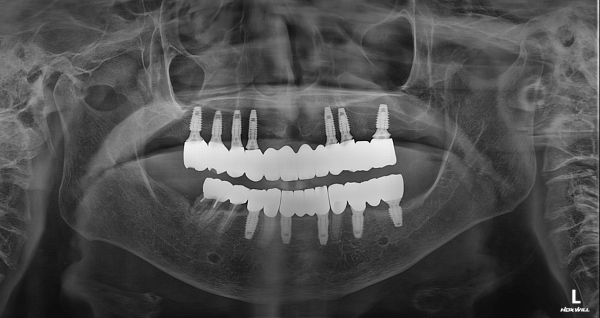

치료 과정

치료 기간 : 2025년 1월 ~ 7월

1월 : 정밀 진단 및 계획

2월 : 임플란트 수술

3~6월 : 골유착 및 경과 관찰

7월 : 전악 고정성 보철 완성

고령 환자 수술에서 가장 중요한 원칙은 단 하나입니다.

“많이 하는 수술이 아니라, 안전한 수술”

최소 절개

짧은 수술 시간

출혈 최소화

정확한 위치 식립

구강악안면외과 전문의의 수술 경험을 바탕으로

부담을 줄이고 안정성을 높였습니다.